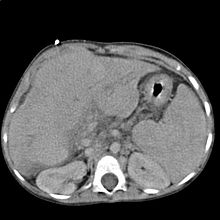

Im Ultraschall stellt sich die Leber inhomogen dar. Der Leberrand ist wellig, die Binnengefäße sind rarefiziert. Der Lobus caudatus kann vergrößert sein. Sehr gut können mit dem Ultraschall ein Aszites und eine Milzvergrößerung (Splenomegalie) erkannt werden. Eine verbesserte Form der Sonographie stellt der sogenannte Fibroscan, auch bekannt als transiente Elastografie, dar. Hiermit kann die Fibrosierung, also der Bindegewebsumbau, der Leber ermittelt werden, was ein sehr zuverlässiges Ergebnis zur Diagnosestellung liefert und zukünftig die Leberbiopsie (s.u.) ersetzen könnte. Mit der Farbduplexsonographie lässt sich in den Lebervenen eine verminderte Elastizität der Leber, in der Pfortader ein verminderter Fluss sowie in der Leberarterie ein erhöhter peripherer Widerstand messen.